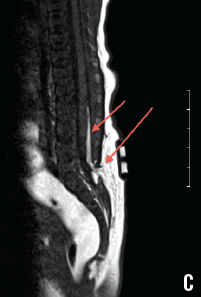

Magnetic resonance imaging (MRI) of the spine (C) confirmed a defect at the posterior elements of L5, and a suspected tethered cord with fat seen in the posterior epidural space.